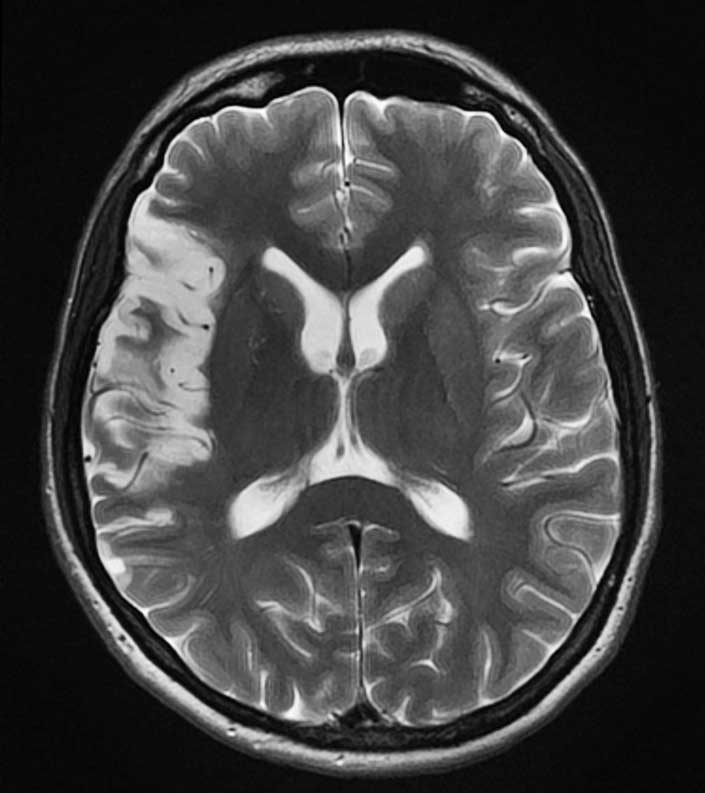

мСКТ, СКТА, МРТ, МРА, рентгенография, маммография

магнитнорезонансном томографе с напряжением магнитного поля 3 Тл

Как и в любых других видах диагностического поиска при радиологическом обследовании, например, мультиспиральной компьютерно-томографической (мСКТ) или магнитнорезонанской (МРТ) томографии, процедура проводится не для того, чтобы найти что-нибудь (не важно что), хотя в процессе проведения случайные находки и встречаются. Основная цель – подтверждение или опровержения наличия вполне определенных изменений. В связи с этим, перед проведением диагностики настоятельно рекомендуется проконсультироваться с врачом.

В отличии от электрофизиологических и ультразвуковых методик, радиологические предоставляют информацию, которая может быть качественно документирована в общепринятых международных форматах. Именно это обстоятельство делает возможным отсроченный анализ томограмм, рентгеновских снимков и т.д., который многие грамотные специалисты предпочитают осуществлять самостоятельно.

Качественная диагностика, тем не менее, складывается из уровня и характеристик используемого оборудования и квалификации персонала (не только врача-рентгенолога, но и лаборантов и техников, т.к. важно получить качественные изображения, пригодные для дальнейшего анализа).